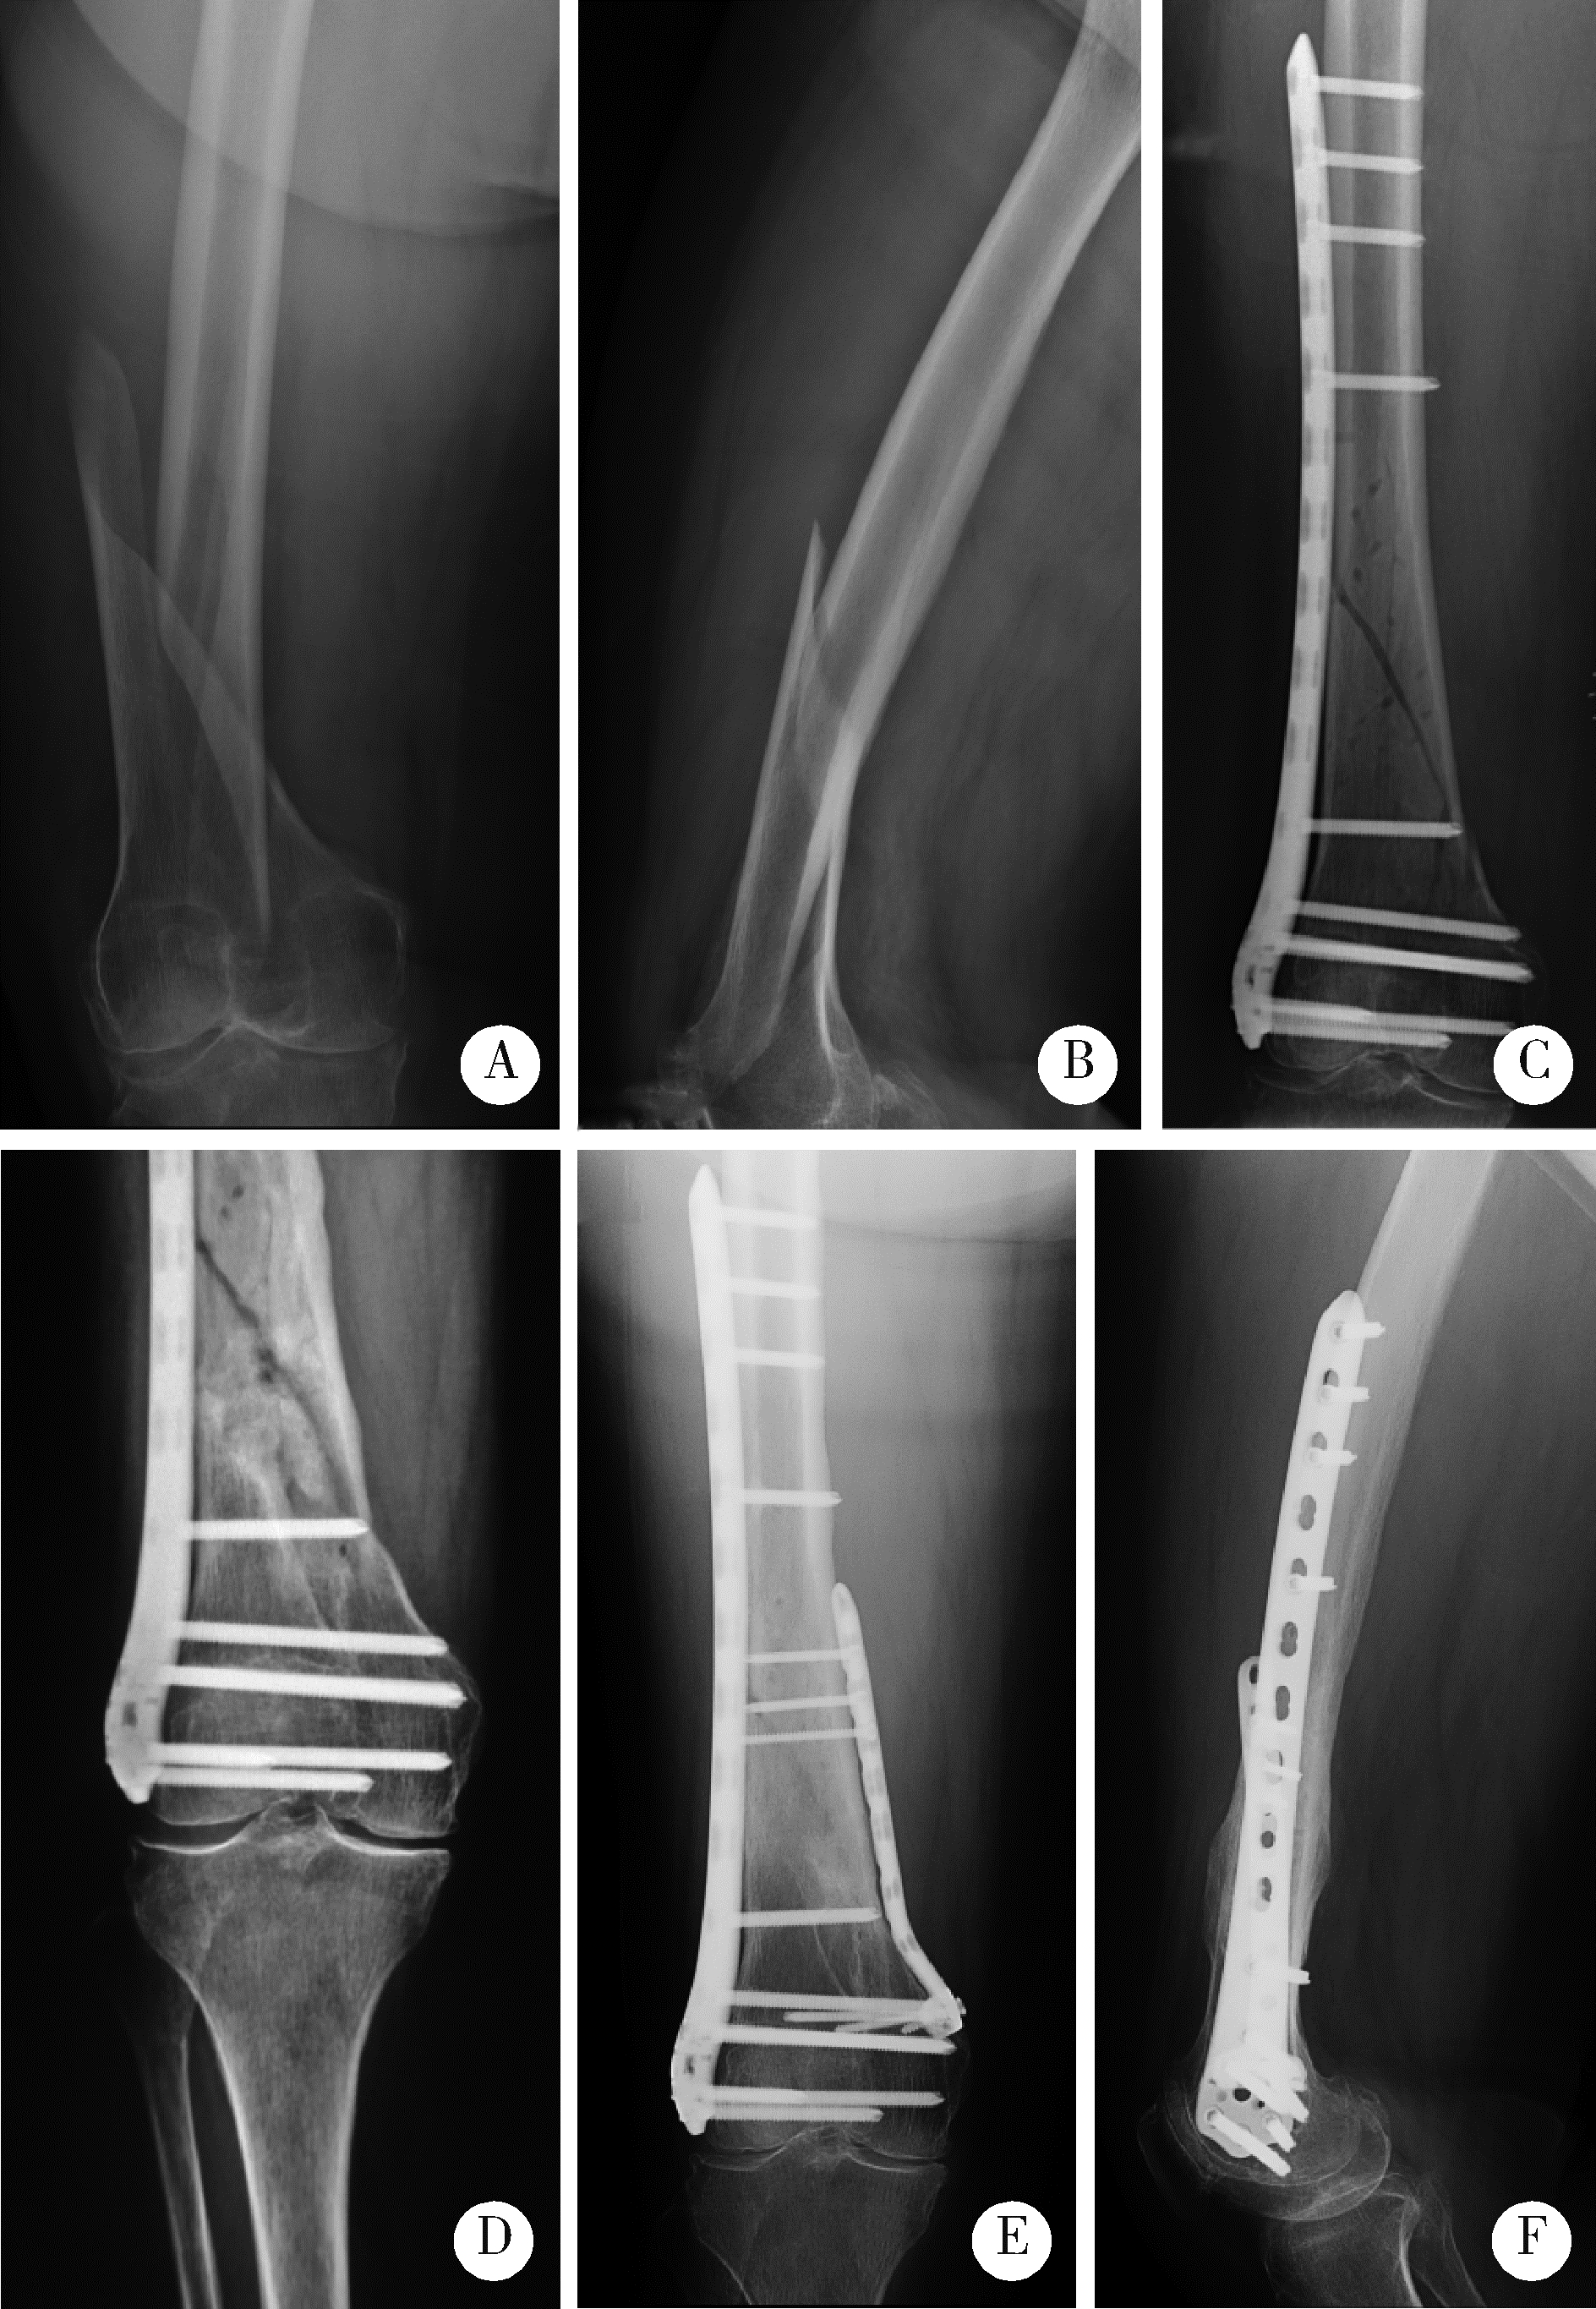

| 图4 女性患者,76岁,摔伤致右侧股骨远端骨折 |

| Figure 4 A 76 years old female patient suffered from the right distal femur fracture caused by fall A, B, preoperative anterior-posterior and lateral X-ray; C, postoperative X-ray after the 1st operation; D, nonunion 12 months after operation; E, F, fracture healing 5 months after revision with medial plate addition and bone graft. |